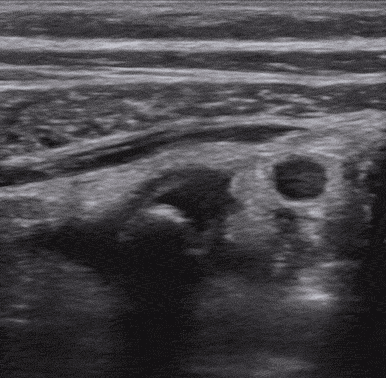

14 yaşında kız-çoçuk hasta, karın ağrısı ile acil servise başvuruyor. Çocuk olması nedeni ile öykü tam alınamıyor ama muayenede yaygın karın hassasiyeti olduğu görülüyor ve sağ kadranlarda daha belirgin hissediliyor. Hemen yanı başınızdaki ultrason ile bakmaya karar veriyorsunuz ve tanıyı koyuyorsunuz.

Ultrason görüntünüz..

Akut apandisit

Akut apandisit en sık görülen cerrahi acillerdendir. Pediatrik ve gebe hastalar ise radyasyon maruziyetinden en çok korkulan ve korunması gereken hasta grubudur. Bu yüzden bu konu ile ilgili fazlaca çalışma bulunmaktadır ve şüpheniz yüksek ise cerrahi konsültasyonu bu hasta grubunda öncelik verilecek yoldur. Acil servis hekimlerince, yapılan bir çalışmada, US ile bu tanı sensitivite %65 ve spesifite %90 oranındadir. Geniş çaplı pediatrik bir çalışmada ise ağrı süresinin artması ile sensitivitenin de arttığı gösterilmiştir.

Akut apandisit US bulguları;

- Halka yüzük görünümü,

- Dilate >6 mm,

- Komprese olmayan,

- Non peristaltik,

- Kör sonlanan tübüler yapı,

- Ek bulgular ise; periapendiküler serbest sıvı, apendikolit, dopplerde artmış vaskülarite